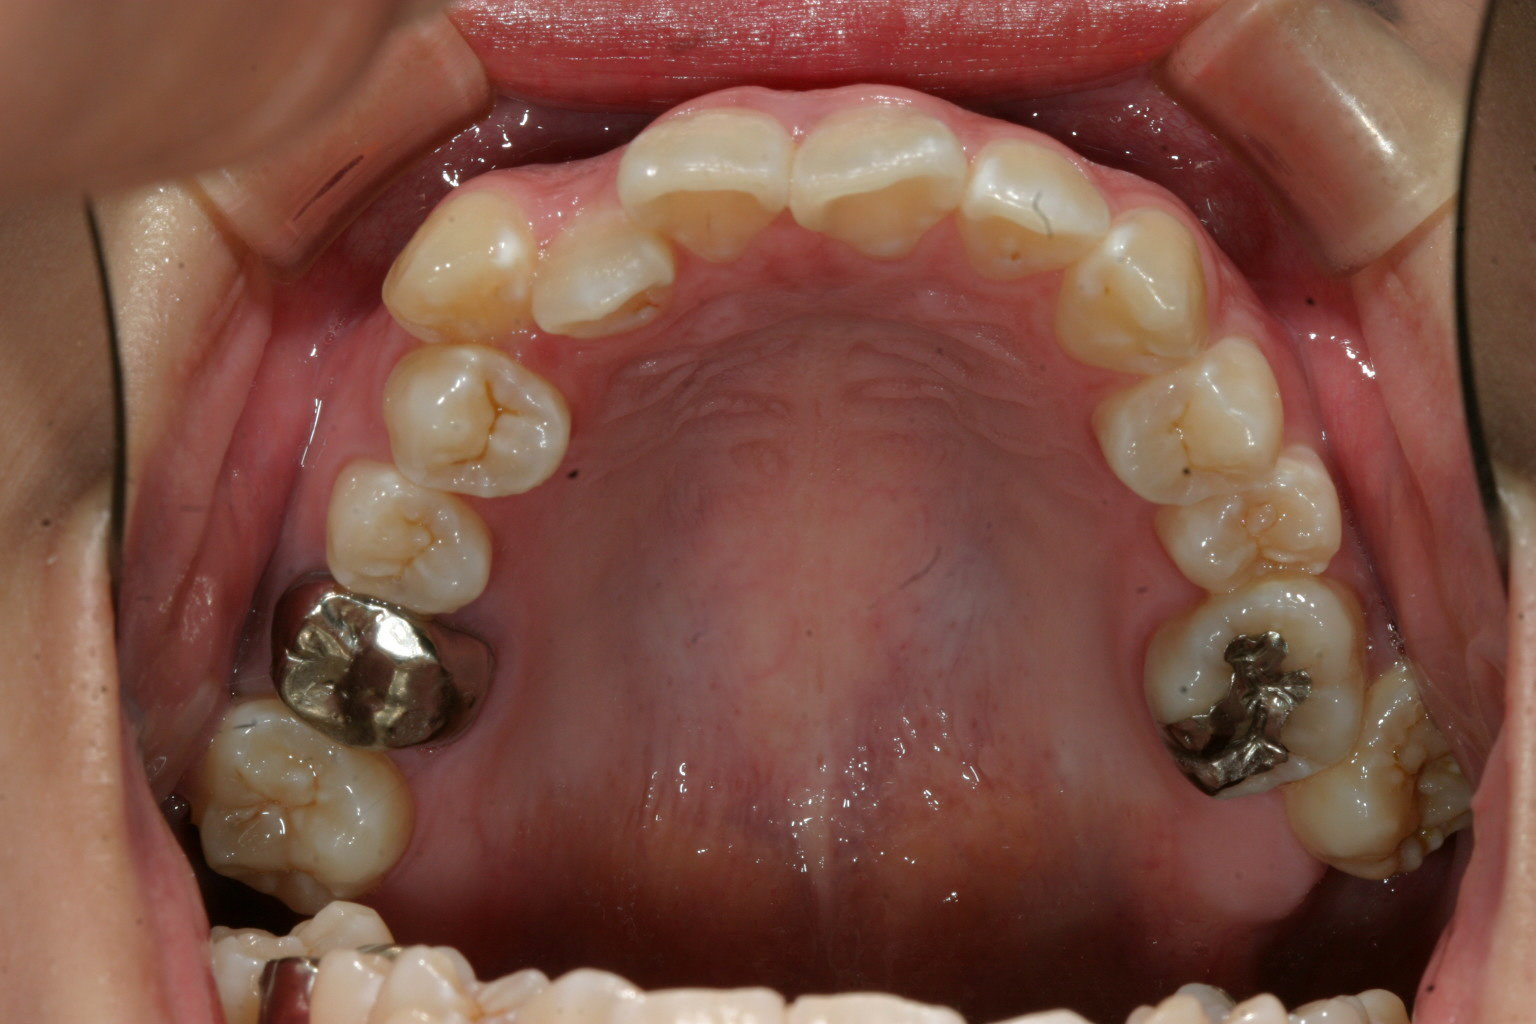

右の八重歯が気になる。

右の八重歯が飛び出してるのが気になりますね~

側面観もガタガタしています。

このケースは非抜歯で犬歯の唇側転移を改善致しました。